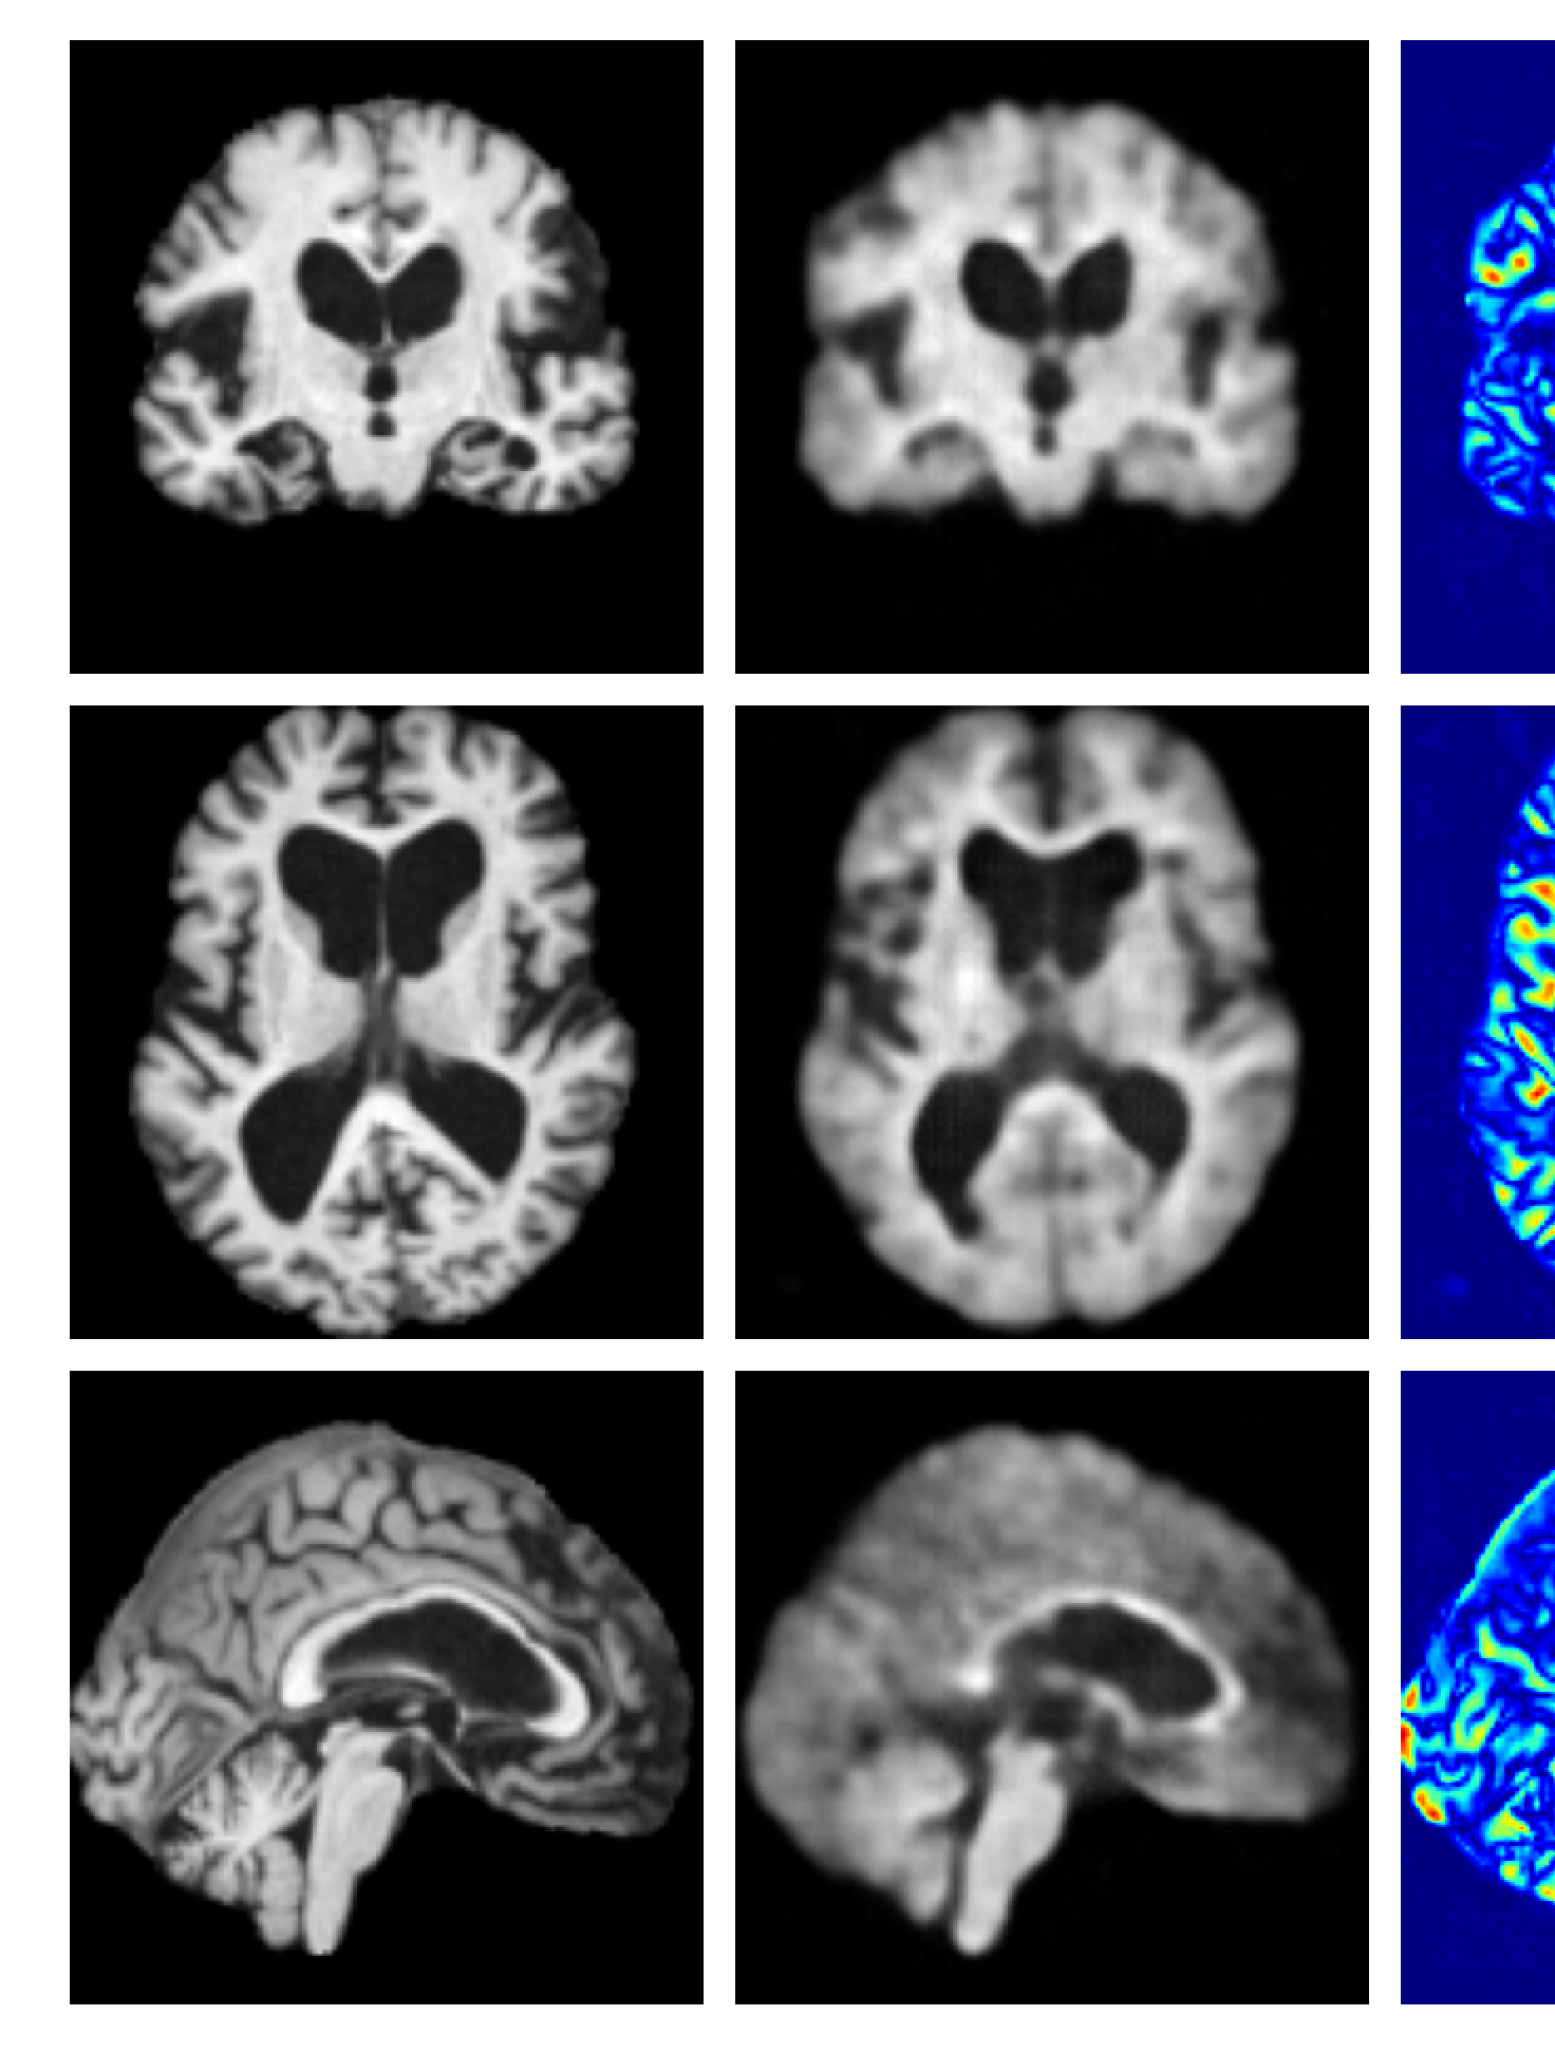

Figures 8 and 9 are enlarged versions of Figures 3 and 4 respectively, with the latter now including results from all compared methods. Figure 10 provides example reconstructions and anomaly maps for an AD subject from the ADNI disease cohort.

Refer to caption

(a) Input

Figure 9: Enlarged example reconstructions and anomaly maps for a sample from the disease cohort of the XXXH dataset. The lesion region is indicated in the original image by the red box.